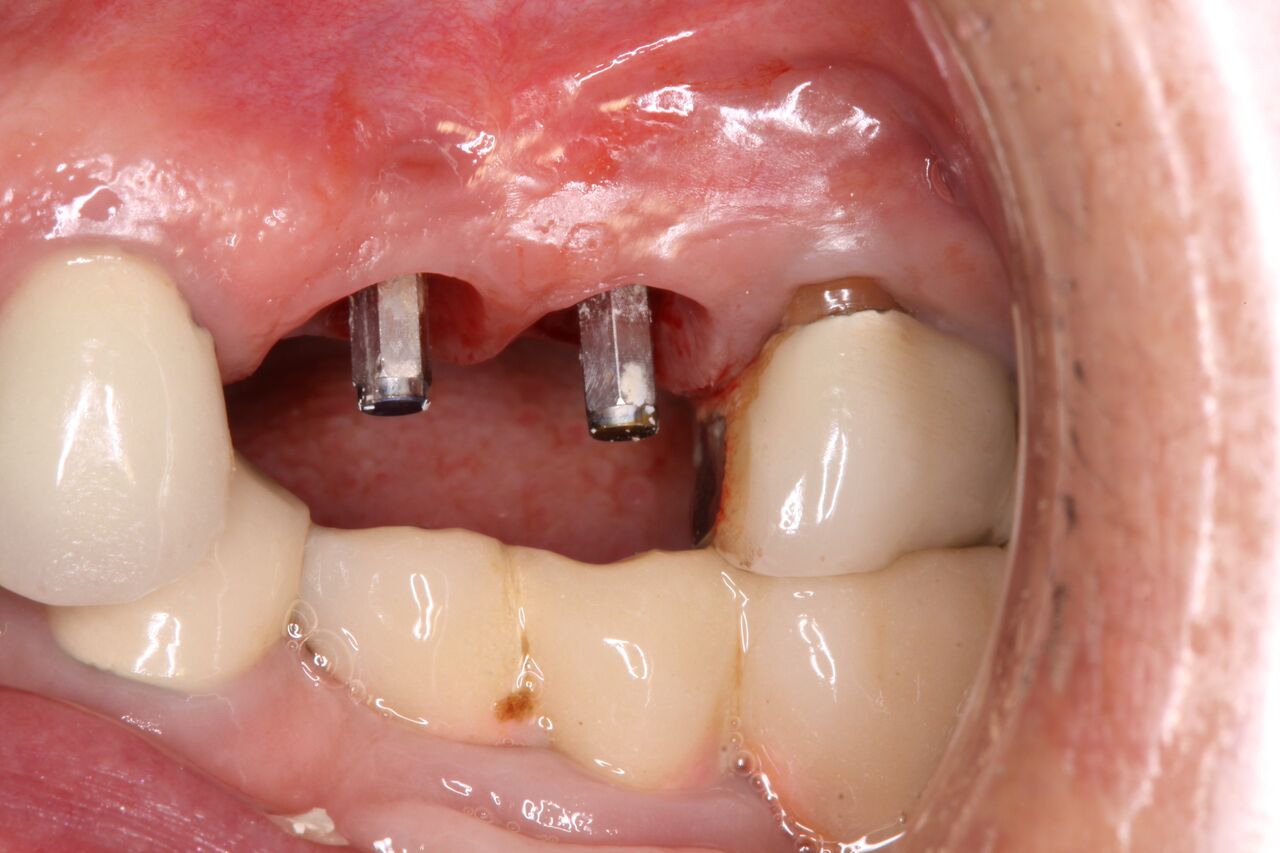

(10.) Initial clinical evaluation of Nos. 12 through 14 after crown on No. 12 and pontic on No. 13 removed.

Figure 10

(11.) Extraction of fractured and decayed No. 12 with periapical granuloma and original

Figure 11

(12.) Extraction of fractured and decayed No. 12 with periapical granuloma and original

Figure 12

(13.) Day of surgery with immediate implants for Nos. 12 and 13 with immediate restoration revised from the original restoration.

Figure 13

(14.) Integration confirmation on Nos. 12 and 13 at 6 months with temporary abutments and good soft tissue maturation.

Figure 14